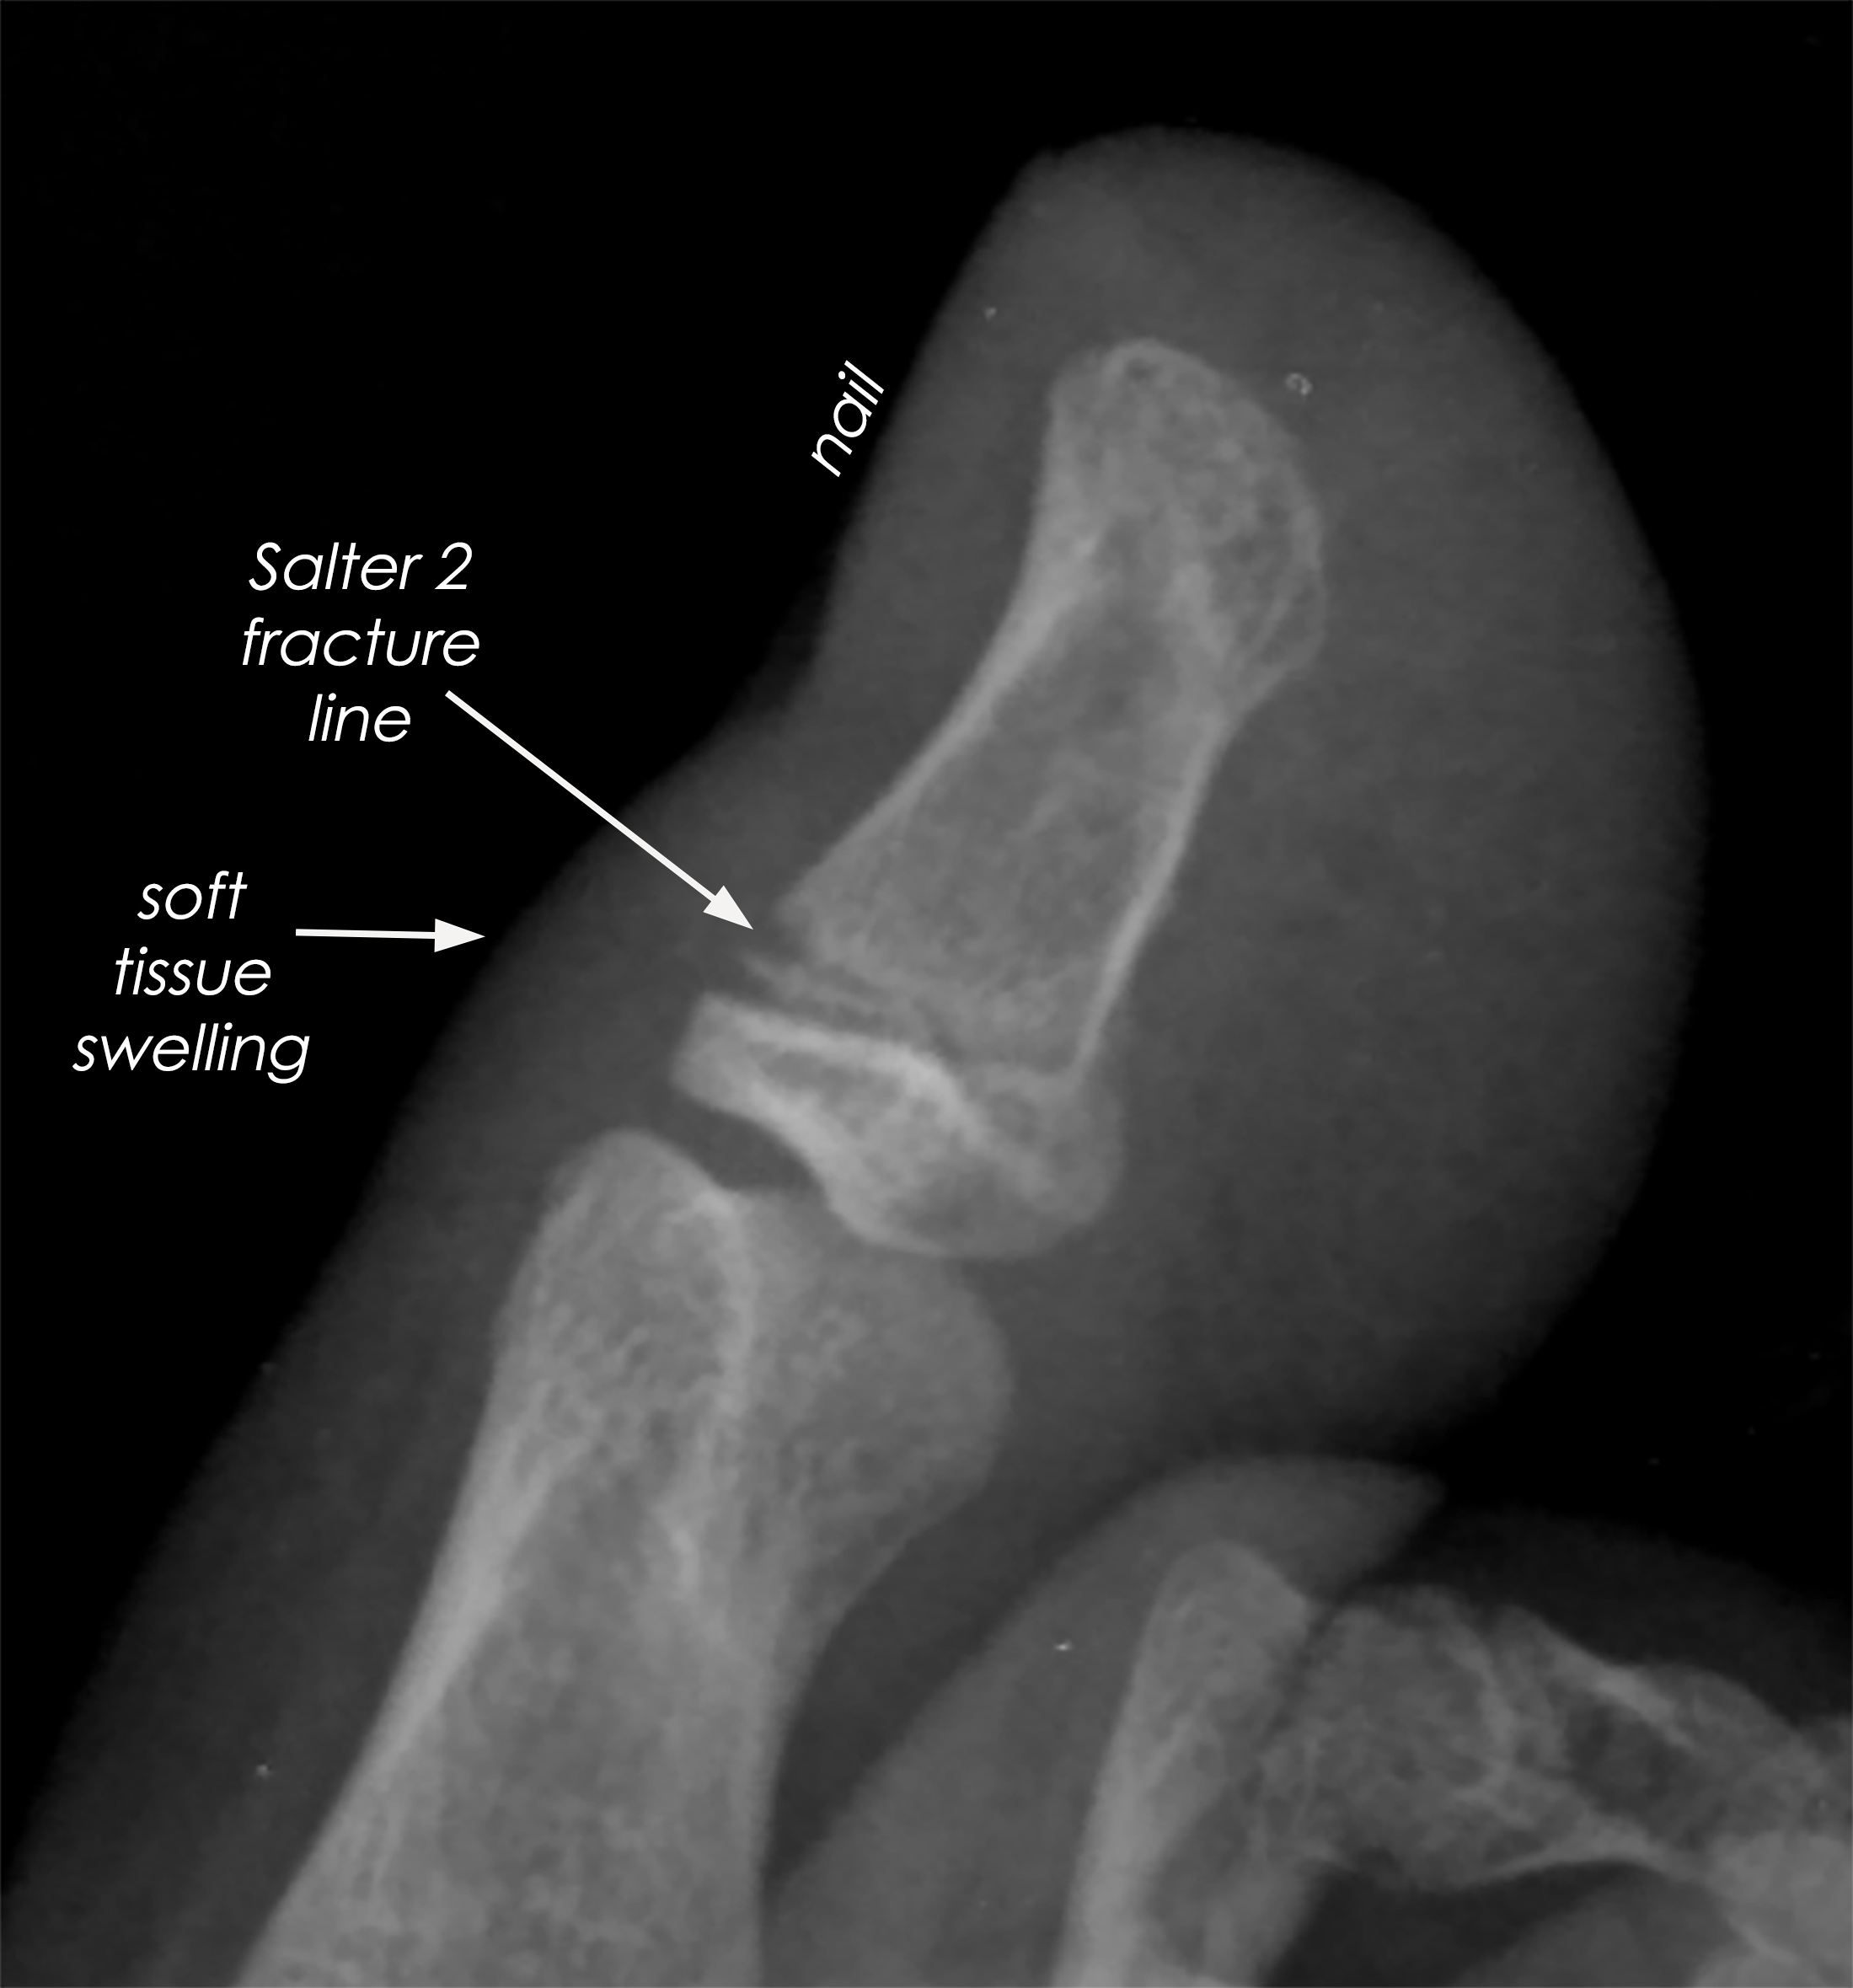

손가락 뼈에 금이 간 경우, 그 정도에 따라 치료 방법이 달라질 수 있습니다.

- 단순 골절: 뼈가 깨지지 않고 비교적 완만하게 금이 간 경우에는 깁스로 고정해주기만 해도 충분할 수 있습니다.

- 복합 골절: 뼈가 여러 조각으로 깨져 있는 경우에는 핀이나 금속판을 사용하여 뼈를 고정해야 할 수 있습니다.

- 비스듬한 골절: 뼈가 비스듬하게 부러진 경우에도 핀을 사용하여 고정하는 것이 일반적입니다.